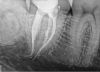

The new technology introduced in this article is based on advanced multisonic technology. Several current systems take advantage of ultrasonics and/or piezoelectric ultrasonic technology to deliver endodontic therapy. Some of these include MiniEndo (Kerr Dental), Varios® (NSK, nskdental.us), and Newtron® (Satelec, A-dec Inc, a-dec.com). The cases documented in this article feature the GentleWave® System (Sonendo®, sonendo.com), which employs a proprietary multisonic cleansing technology to deliver therapeutic irrigants into the root canal system, including lateral canals and tubules of complex root canal systems, while leaving the dentin largely intact.1,6-11 In the case shown in Figure 2 (preoperative radiograph) and Figure 3 (postoperative), the clinician was initially under the misconception that simple "cleaning and shaping" could be used for the root canal system in the conventional manner. The clinician evaluated the root canal system digitally in 2D and 3D before starting the case. The case was accessed, prepared, and cleaned and disinfected. Special attention to the digital imagery of the mesiobuccal root complex allowed the clinician to appreciate that the MB1 and MB2 merged before exiting from a common foramen. The 2D postoperative radiograph (Figure 3) illustrates that all of the mechanical objectives were realized.

Fig 2. Preoperative (Fig 2) and postoperative (Fig 3) radiographic images.

Figure 2

Fig 3. Preoperative (Fig 2) and postoperative (Fig 3) radiographic images.

Figure 3